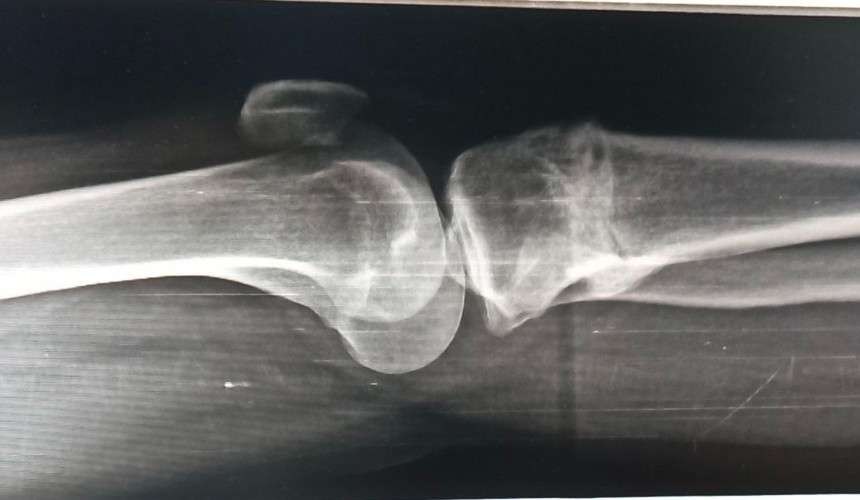

Сибирский государственный медицинский университет приступил к серийному производству нового материала для восстановления костной ткани. Разработку создали совместно с компанией «НПК Синтел», а после внесения вуза в реестр производителей медицинских изделий началось промышленное производство.

Новый материал представляет собой композитные гранулы из полилактида и гидроксиапатита. Особенная полимерная оболочка сохраняет форму гранул и создаёт прочную основу для роста кровеносных сосудов и костной ткани.

Сейчас специалисты завершают доработку состава и формируют оптимальную структуру гранул. Следующим этапом станут клинические испытания, которые должны подтвердить эффективность материала для восстановления костей, сообщает «Сибирский новостной».